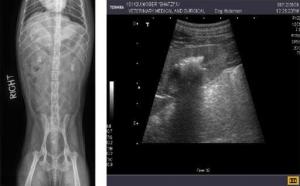

Ультразвуковое исследование почек у кошек проводится в рамках исследования состояния мочевыделительной системы. В свою очередь, мочевыделительная система диагностируется при проведении УЗИ брюшной полости. УЗИ почек проводится при любых симптомах, связанных с нарушением мочеиспускания — когда...

УЗИ брюшной полости у кошки — одна из наиболее востребованных диагностических процедур для домашних любимцев. Кошка не может пожаловаться на то, что у нее что-то болит, часто хорошо скрывает болевые ощущения, или, наоборот, очень бурно реагирует на любые прикосновения. УЗИ позволяет проверить сос...